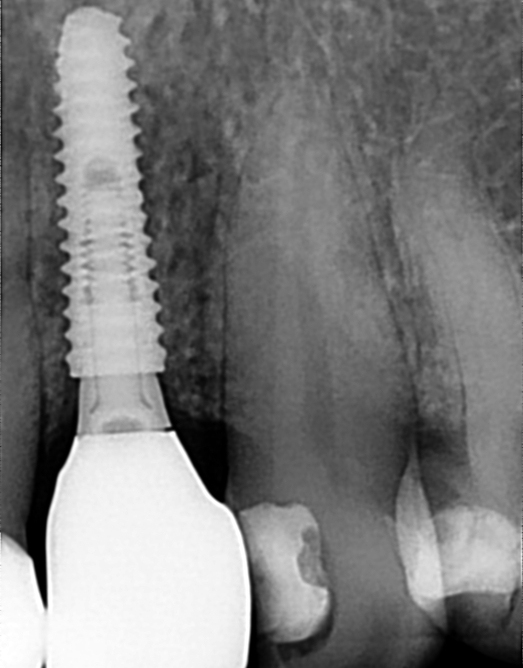

Regenerativni parodontološki zahvat kojim se kirurškim putem regenerirao infrakoštani defekt(parodontološki džep)